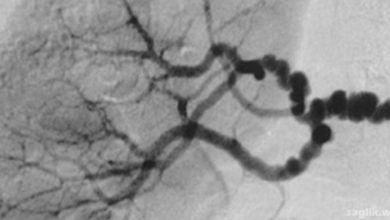

Fibromüsküler Displazi Nedir? Belirtileri, Nedenleri, Tedavisi

Fibromüsküler displazi (fibromuscular dysplasia, FMD), vücuttaki bir veya daha fazla arterin duvarında anormal hücre gelişimine neden olan bir hastalıktır. Arterler,…